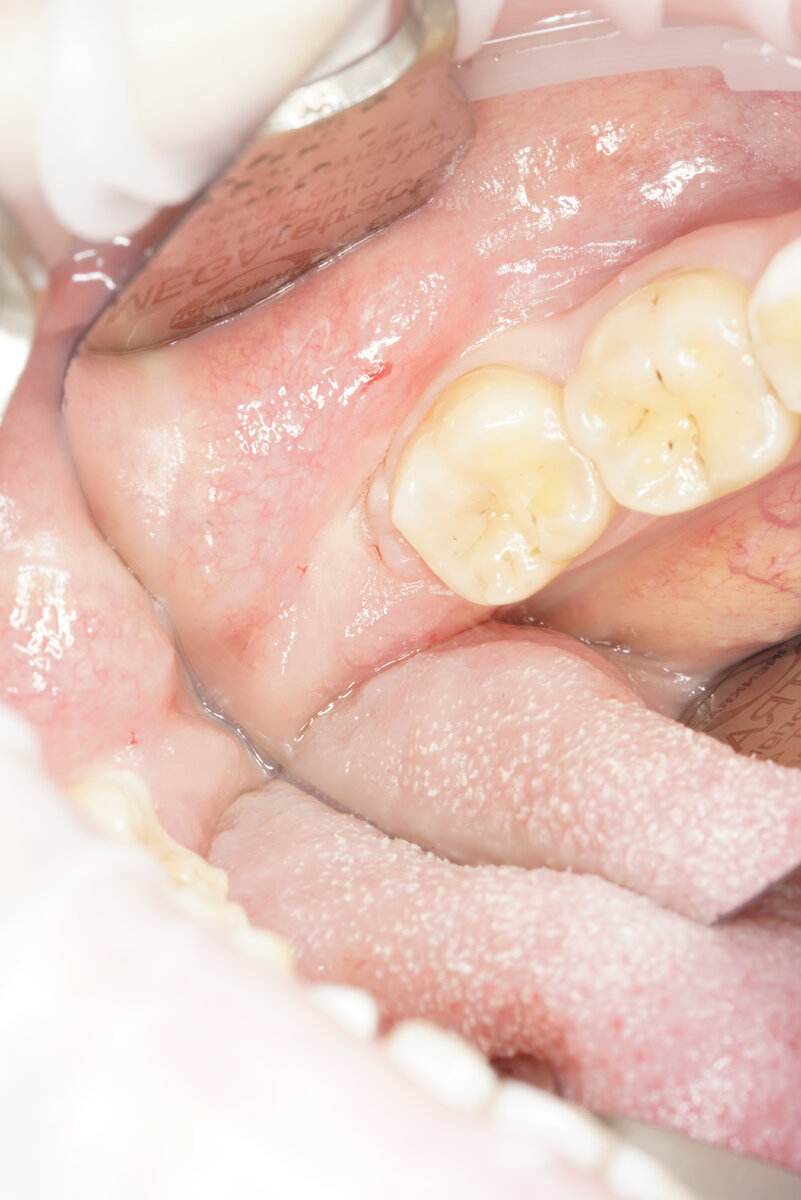

Сразу скажем, что правильно и ровно, а уж тем более в паре с антагонистом зубы мудрости вырастают не так уж и часто. Но даже при таком раскладе они могут стать источником проблем – и вновь из-за своей труднодоступности. Увы, даже передние зубы большинство людей чистит не идеально – что уж говорить о восьмерках. В итоге мы получаем кариес – в лучшем случае только на восьмерке, в худшем – также и на соседней семерке.

Но даже если врач возьмется вылечить зуб мудрости, сделать это качественно будет очень сложно: зуб плохо видно, к нему так просто не подобраться, сложно наложить коффердам и пролечить каналы. И все равно все может закончиться удалением – в случае повторного кариеса, пульпита или периодонтита. И, выходит, пациент зря тратил свое время и деньги на лечение. Но не будем грешить на алчность или недальновидность доктора - например, когда я училась в университете, нас учили, что выросшие восьмерки все же стоит сохранять. Зачем?